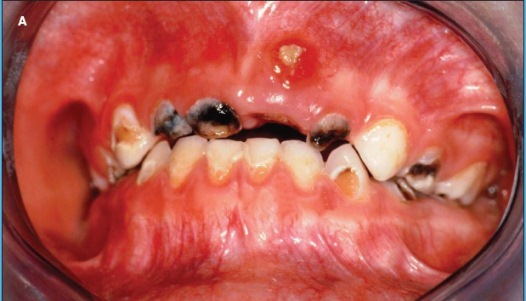

A pediatric resident recommends an extensive evaluation for a 5-year-old girl who presents with a 1-week history of a neck mass and no other symptoms. According to the resident, physical examination findings are normal except for a 4 ×2-cm tender submandibular lymph node on the left. Before ordering laboratory and imaging studies, the attending pediatrician inspects the patient's teeth and finds multiple sites of dental decay and a deep, black cavitated lesion in a left mandibular molar. Severe dental decay is the likely cause of the lymphadenopathy. Antibiotics are prescribed, and the patient is referred to the pediatric dentist for definitive diagnosis and treatment.

Often touted as the most common chronic disease of childhood, ECC is defined as decay in the primary teeth of children aged 71 months or younger.1 Surveillance during 1999 to 2002 in the United States found that 41% of children aged 2 to 11 years had dental caries in their primary teeth.2 Approximately one fifth of these children had untreated tooth decay.2 Nonhispanic white children and those from higher-income families had the lowest rate of caries.

When inspecting a child's mouth, look for cavitated or noncavitated dental lesions, dental fillings, and missing teeth. The presence of gingivitis and/or plaque, chalky white spots, or deep fissures on the teeth are evidence of dental decay.9 Refer any child with worrisome findings to the pediatric dentist.

| The Pathophysiology of Dental Caries: A Brief Review The cause of early childhood caries (ECC) is multifactorial, but the 2 main culprits that interact at the tooth surface to produce ECC are dietary sugar and bacteria—particularly Streptococcus mutans. Infants are known to acquire S mutans from their mothers or primary caregivers in the first 2 years of life.29,30 Exposure to sugary drinks from a bedtime bottle or frequent consumption of carbonated soft drinks31 places young children at increased risk for dental decay. The acidic by-products of the bacterial metabolism of sugary substances lead to the development of plaque. Plaque adheres to the tooth surface and causes dental demineralization or the leaching out of important minerals (ie, calcium, phosphate, and carbonate) (A). ![]() Untreated dental caries can lead to periodontal abscesses (B). Because of the adjacent location of anatomic structures, facial cellulitis (C) and maxillary sinusitis may result from direct extension of the odontogenic infection, which causes tissue breakdown and bone resorption.32 Further extension of this infectious process could potentially affect intracranial structures, leading to brain abscess or orbital cellulitis. Untreated odontogenic infections can also lead to Ludwig angina—a rare severe condition involving extension of infection into the floor of the mouth and beyond, with potential airway compromise.33 ![]() As with all odontogenic infections, the most common causative agents are anaerobes and Streptococcus and Staphylococcus species. A patient with signs and symptoms of Ludwig angina (neck and/or mouth pain and swelling, trismus, fever, malaise, fetid breath) must be treated emergently to ensure a secure airway. Surgical debridement as well as administration of broad-spectrum antibiotics with adequate anaerobic coverage provide definitive treatment.33 ![]() |